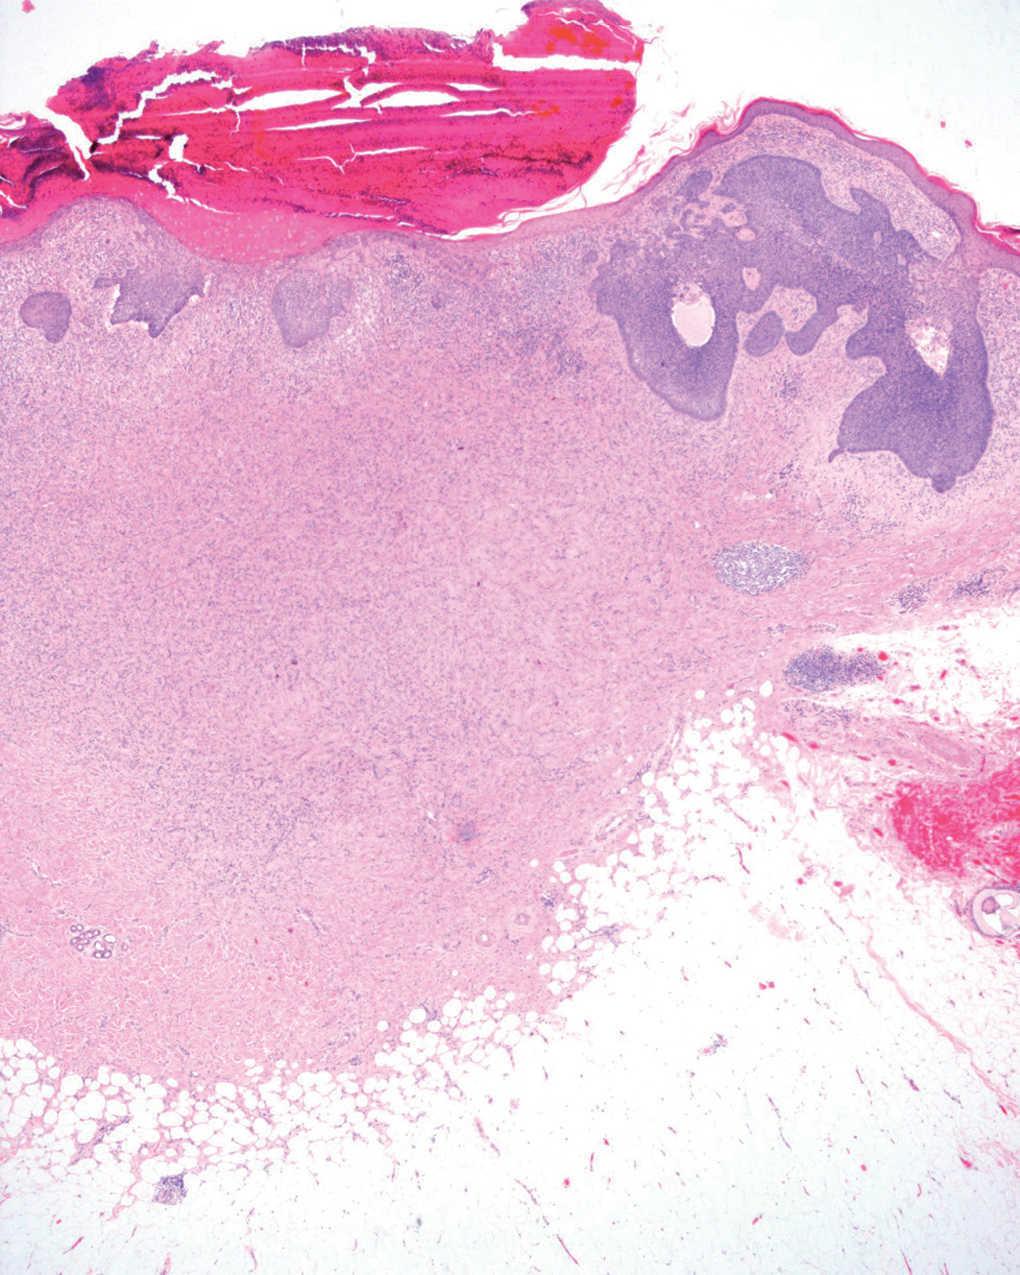

Se realizó extirpación completa de la lesión y se observó en el estudio anatomopatológico un nódulo dérmico localizado en dermis reticular, formado por una proliferación mesenquimatosa de células fusiformes sin atipias, con un patrón vagamente estoriforme. Entre ellas se apreciaban algunos histiocitos xantomizados, linfocitos y fibras de colágeno (fig. 1). Superficial a este nódulo se observó una proliferación epidérmica de células de hábito basaloide, que crecían en la dermis papilar formando pequeños nidos sólidos limitados por una capa de células en empalizada. Focalmente esta proliferación formaba nidos de mayor tamaño que infiltraban la dermis reticular. Algunos tenían degeneración quística central (fig. 2) y hendidura de separación con la dermis adyacente (fig. 3). Los cambios descritos en la epidermis eran idénticos a los observados en el carcinoma basocelular, y la proliferación fibrohistiocitaria presente en la dermis era diagnóstica de dermatofibroma.

Fig. 1.--Proliferación de células fusiformes con patrón estoriforme localizada en la dermis reticular sobre la que se aprecia una proliferación epidérmica de células basaloides. (Hematoxilina-eosina, x4.)